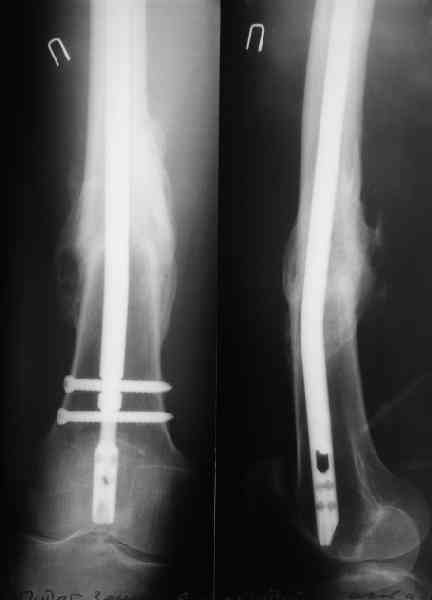

В приложении как раз видна эволюция использововшихся у нас большеберцовых гвоздей. Первый - дизайн как у UTN, второй - разнесены 45 градусные отверстия (зачем их вообще изначально так нелепо на одном уровне сделалм???), третий - убрано сиавшее лишним статическое отверстие, Herzog's bend перемещен более проксимально.

Забавненько смотрится... "век живи, век учись", как говорится. А чья мысль использовать блокируемые штифты для б/берцовой кости при переломах бедра? Такое встречалось где-то в литературе или это ваше ноу-хау?

> Забавненько смотрится... "век живи, век учись", как говорится.

Некоторые этот вариант воспринимают чуть ли не как покушение на святое, мол, если "Дарованная Нам Свыше Оригинальная Методика" не предусматривает такое, то это ересь и крамола. Хотя тут все самоочевидно - необходимый результат достигается.

Насколько я помню, мы использовали этот вариант после знакомства с гвоздями SIGN, которые вообще одинаковые для бедра и голени, и дизайн у них большеберцовый.